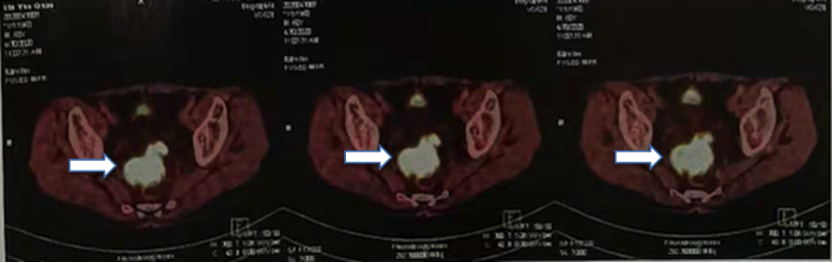

(4)2020-4-30 PET-CT:直肠前壁明显增厚,突出于肠壁呈团块状占位,FDG代谢显著异常活跃,部分坏死,考虑恶性肿瘤;盆腔中份、左侧盆壁及直肠左侧见淋巴结显影,FDG代谢异常活跃,考虑直肠肿瘤淋巴结转移。

2020-12-16 18 F-FDG PET/CT提示:直肠壁未见确切异常增厚及糖代谢异常增高,盆腹部淋巴结未见增大及糖代谢异常增高;肝囊肿。